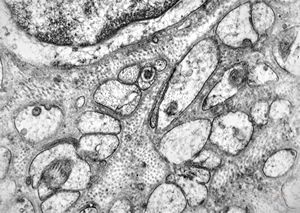

F, 39y. | collagenous and elastin fibers from corium

F, 39y. | collagenous and elastin fibers from corium

F,68y. | collagenous and elastin fibers from corium